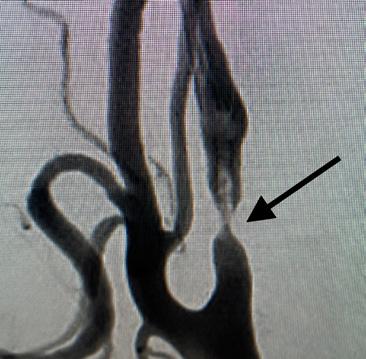

The carotid artery is a major blood vessel that brings blood from your heart to your brain. There are normally two carotid arteries, one on the right side and one on the left. At the point where the carotid artery divides into a branch that feeds the face and a branch that feeds the brain, there is a natural location for the buildup of debris, called atherosclerotic plaque.

As plaque buildup increases, it takes up more space within the vessel and begins to narrow the path for blood flow through the vessel. This narrowing is called stenosis. Because plaque buildup is typically disorganized, bits of plaque can tear off or rupture. When a plaque ruptures, it may cause a stroke.

Patients with plaque buildup who develop stroke-like symptoms, or an actual stroke are referred to as having “symptomatic” disease, because the plaque is believed to have caused their symptoms.

In contrast, patients with plaque buildup who have never had symptoms before are referred to as patients with “asymptomatic” disease. Patients with asymptomatic disease may be identified during a physical examination when a “whooshing” sound or bruit is heard over the carotid artery or when an imaging study of their neck is done for another reason. In general, the worse the carotid stenosis, the higher the chance of a stroke.